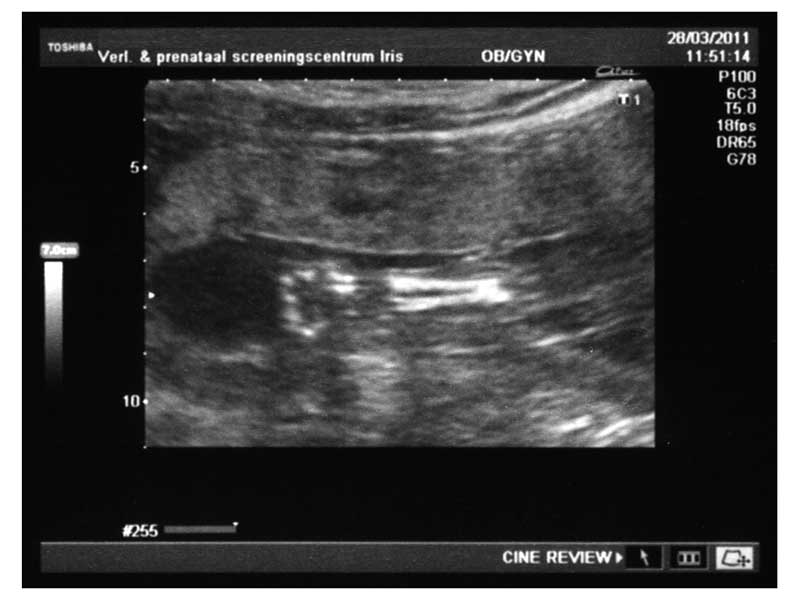

Hier zijn 2 toch best wel aardige echo's. De bovenste is een armpje met handje, en de onderste is het hoofdje.

Deze echo was minder leuk dan voorgaande. Niet dat ik me nu direct veel zorgen ga maken - ik heb vooral onduidelijkheid en wat puntjes die buiten het gemiddelde lagen gehoord - maar omdat juffie zich er wel zorgen over aan het maken is.

Nu maar hopen dat we snel in het UMC terecht kunnen om duidelijkheid te krijgen.